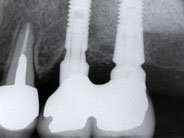

7年前に右下顎にインプラントを入れました。

入れ歯に較べて、人生が変わるほど何でも食べられる、と喜んでいただいています。

X線的にも何の問題も無く経過しており、平気で10年持ちそうです。